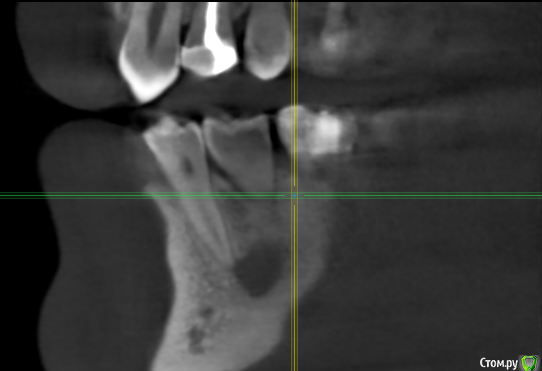

kramer Опубликовано 2 мая, 2018 Поделиться Опубликовано 2 мая, 2018 Коллеги! Помогите, пожалуйста, советом. Пациент обратился с жалобами на зуб 36, характерными для периодонтита (дискомфорт при накусывании, периодические обострения и т.д.). Зубы 35,34 интактные. Сделал КТ, вот что там: Синус-тракт в области 36: Область 35: Мезиально очаг поражения достигает апекса 34 и, видимо, уже частично разрушил компактную пластинку: Если это обычный периодонтит, то 1) почему такие странные очертания очага (или не странные?) 2) с 36 все понятно, но как могли быть поражены 35 и 34? Ссылка на комментарий

kramer Опубликовано 3 мая, 2018 Автор Поделиться Опубликовано 3 мая, 2018 Вы боитесь онко? Когда симптоматика появилась? Когда шестой лечили? Свищ есть или он неактивный сейчас? После лечения шестого симптоматика сохранялась? Есть снимки любые в этой области раньше? Как лимфоузлы? Я считаю, что это хр. гранулирующий периодонтит, согласен с вашим диагнозом. Вопрос только от пятого или от пятого и шестого (моляр недопломбирован).36 лечен давным давно, свищ не активен. Я думаю, периодонтит 36 вследствие неудовлетворительного эндо. Мне неясно, почему поражены 34 и 35. Изначально пациент пришёл с прицельным снимком, на котором видна эта "амеба". Дифдиагноз был между периодонтитом, травматической костной кистой и кератокистой. Вариант 2 отпал после КТ, т.к. компактная пластинка оказалась разрушена у апексов упомянутых зубов. Ссылка на комментарий

TIGER Опубликовано 3 мая, 2018 Поделиться Опубликовано 3 мая, 2018 Коллеги! Помогите, пожалуйста, советом. Пациент обратился с жалобами на зуб 36, характерными для периодонтита (дискомфорт при накусывании, периодические обострения и т.д.). Зубы 35,34 интактные. Сделал КТ, вот что там: раф1.png Синус-тракт в области 36:раф2.png Область 35:раф3.png Мезиально очаг поражения достигает апекса 34 и, видимо, уже частично разрушил компактную пластинку:раф4.png Если это обычный периодонтит, то 1) почему такие странные очертания очага (или не странные?) 2) с 36 все понятно, но как могли быть поражены 35 и 34? Гранулирующий периодонтит от 6 зуба.... Ссылка на комментарий

Nazim_NV86 Опубликовано 5 мая, 2018 Поделиться Опубликовано 5 мая, 2018 Во первых периодонтит старый. Корни деформированы. Во вторых тип кости такой, поэтому и очаг такой. Об эндо уже поздно говорить. Ссылка на комментарий